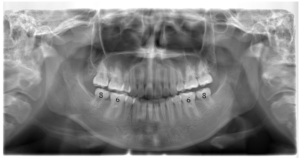

(治療後:写真右)

きれいなスマイルラインとなり、横顔も大きく改善しました。